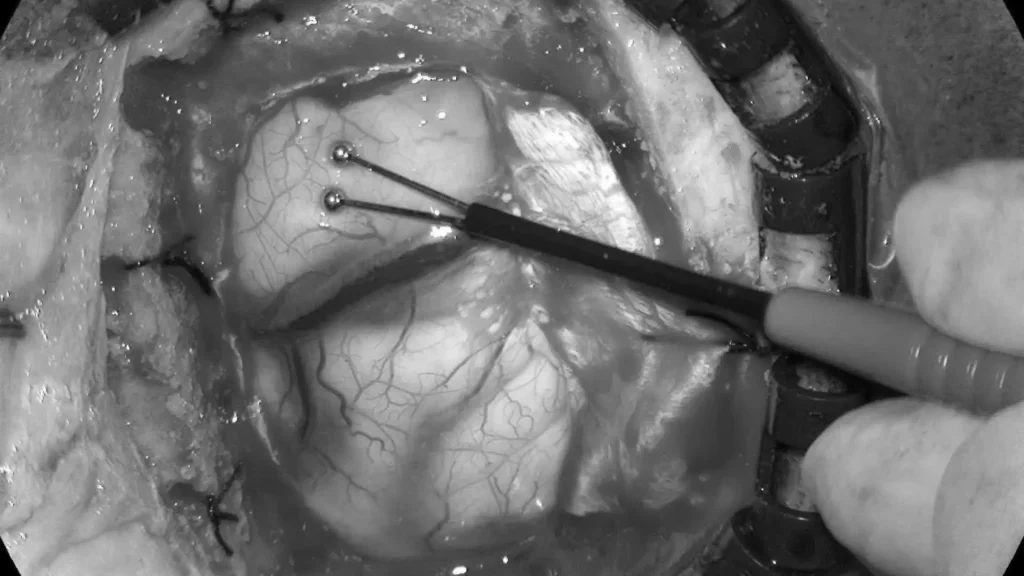

案例(三):血管瘤破裂流血导致肢体无力49岁的女士,接种疫苗后2周感到左腿无力,虽然看了中医和骨科医生,更做了脊柱磁力共振MRI造影, 仍然找不到原因。脑血管外科医生经过临床评估后为她进行了3D三维立体磁力共振脑血管造影,显示其大脑都有先天性动静脉畸形血管瘤并且已经少量出血,瘀血压着她右脑负责控制左腿功能的位置。在3D三维立体电脑导航、运动神经脑皮层反射和连续脑功能监测系统下,神经血管外科医生在显微镜下彻底切除血管瘤和去除瘀血,病人脑部的神经功能得以完好恢复。手术后,病人左腿的力量恢复正常。 | ||

![]() | ||

![]() | ![]() | |

使用运动皮层映射和连续脑功能监测系统进行手术 | ||